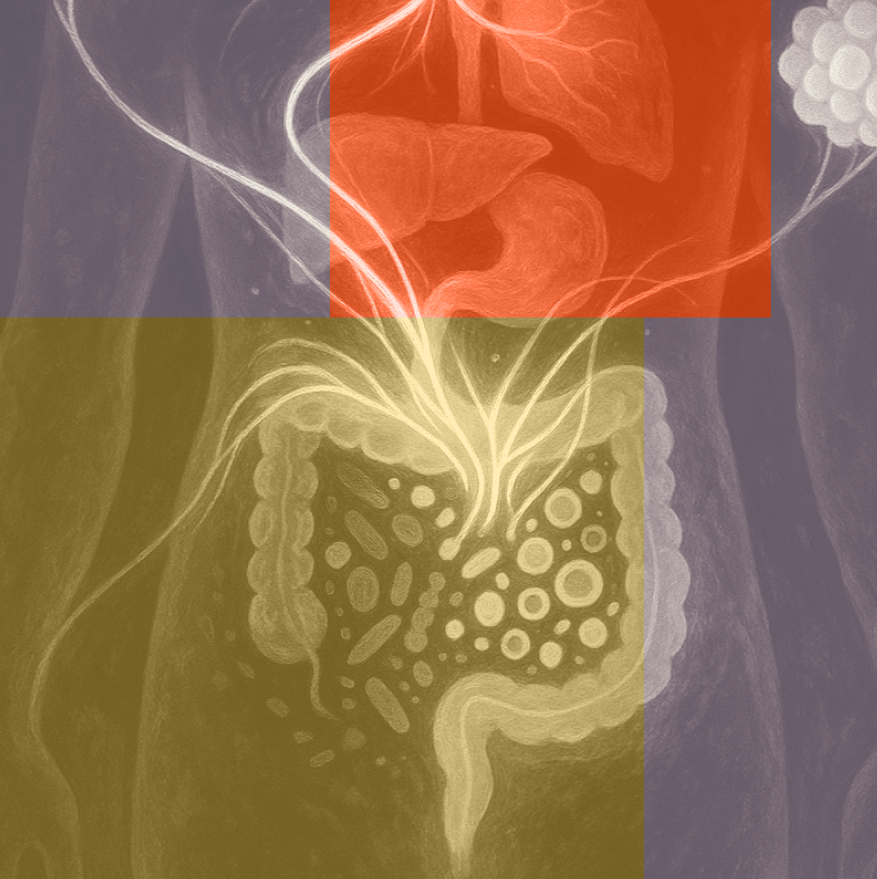

Darmmicrobiota

De darmmicrobiota bestaat uit miljarden micro-organismen, waaronder bacteriën, virussen, gisten en schimmels. Deze microben vervullen essentiële functies in onze gezondheid, van energiestofwisseling tot emotionele en mentale gezondheid. De bacteriële component van de darmmicrobiota is het best onderzocht, met name de balans tussen bacteriën die geassocieerd worden met gezondheid en die in verband worden gebracht met ziekte of ontstekingen. Onderzoek naar de rol van de darmmicrobiota in onze gezondheid laat zien dat deze de metabole gezondheid beïnvloedt.9,10

Een gezonde darmmicrobiota wordt gekenmerkt door een grote diversiteit aan bacteriën en andere micro-organismen die in de darmen leven.11–13 De darmmicrobiota kan invloed uitoefenen op het metabolisme via meerdere mechanismen, zoals de productie van de korteketenvetzuren (KKVZ) acetaat, propionaat en butyraat middels fermentatie van voedingsvezels.11,14,15 Deze vetzuren verbeteren de darmbarrièrefunctie, stimuleren hormonen als glucagon-achtig peptide 1 (GLP1) en peptide YY (PYY) en remmen ontstekingsprocessen. Daarnaast beïnvloedt de darmmicrobiota de productie van galzuren16, de opname van micronutriënten17 en het functioneren van het centrale zenuwstelsel via de zogenaamde darm-hersenas18, alsmede het verzadigingsgevoel, de energiebalans en de vetstofwisseling.19

Verstoringen in de samenstelling en functie van de darmmicrobiota kunnen tot gevolg hebben dat de diversiteit afneemt. Dit leidt tot verstoringen in metabole routes die hormoonregulatie, ontstekingsmodulatie en energiestofwisseling beïnvloeden. Een veranderde samenstelling van de darmmicrobiota, ook wel een dysbiose genoemd, wordt in verband gebracht met insulineresistentie en laaggradige ontstekingen, twee centrale mechanismen bij metabole aandoeningen.20–23 Een verminderde aanmaak van KKVZ, verhoogde doorlaatbaarheid van de darmwand en verhoogde verplaatsing van bestanddelen uit de darm naar de bloedbaan liggen daaraan ten grondslag.

Darm en immuunactivatie

Een van de belangrijkste functies van de darm is het vormen van een selectieve barrière tussen de inhoud van de darm en de rest van het lichaam. Deze darmbarrière bestaat uit een slijmlaag, epitheellaag, tight junctions (celverbindingen tussen epitheelcellen) en immuuncellen. Bij een gezonde darm is deze barrière intact, laat selectief voedingsstoffen door naar het lichaam en voorkomt dat schadelijke stoffen het lichaam binnendringen. Darmbacteriën ondersteunen de slijmlaag en helpen bij het reguleren van ontstekingsprocessen. Een evenwichtige darmmicrobiota is essentieel voor het handhaven van een gezonde darmbarrière.24

Bij dysbiose van de darmmicrobiota en schade aan de darmwand kan de doorlaatbaarheid van de darm toenemen. Hierdoor kunnen bacteriële onderdelen, zoals lipopolysacchariden (LPS) uit de celwand van gramnegatieve bacteriën, in de bloedbaan terechtkomen.25 LPS activeren het immuunsysteem en leiden tot een toename van inflammatoire cytokinen zoals TNFα en IL6. Deze cytokinen spelen een cruciale rol in de ontstekingsreactie. De ontstekingsreactie kan echter uitmonden in chronische laaggradige ontstekingen bij voortdurende blootstelling aan LPS, zoals bij een verhoogde darmdoorlaatbaarheid. Dit draagt bij aan het ontstaan van insulineresistentie, ook wanneer de bloedsuikerwaarden nog normaal zijn. Daarom is het essentieel om een gezonde darmbarrière te behouden om zo chronische ontstekingen tegen te gaan.26